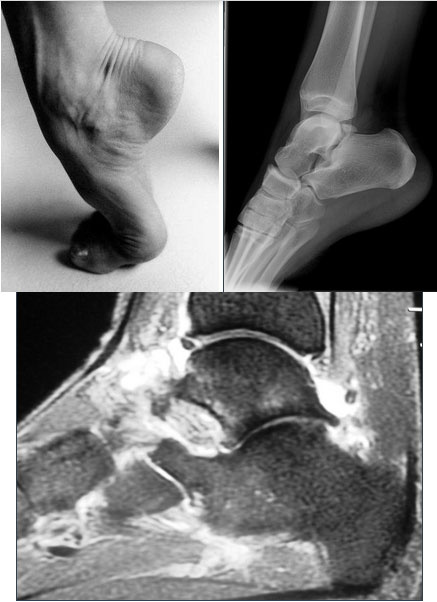

Hálux Rígido

O hálux rígido é uma patologia que afeta a articulação metatarsofalangeana do hálux, promovendo uma alteração degenerativa que leva à perda progressiva da mobilidade articular. Sua etiologia ainda não está totalmente definida, porém, pode estar relacionada a episódios de trauma, mas também pode estar associada a um primeiro metatarso elevado (verticalizado).

Os principais sinais e sintomas clínicos são dores na articulação metatarsofalangeana, perda progressiva da mobilidade e incapacidade ou dificuldade para usar salto, além de uma saliência dorsal. Existem vários níveis de gravidade, e o tratamento se baseia no aspecto clínico e radiográfico. Além disso, indicamos o tratamento conservador nos casos mais leves e em indivíduos com pouca perda da qualidade de vida. O tratamento cirúrgico pode variar de uma queilectomia (limpeza articular) aberta ou artroscópica as cirurgias mais complexas como osteotomias e artrodese (fusão articular).